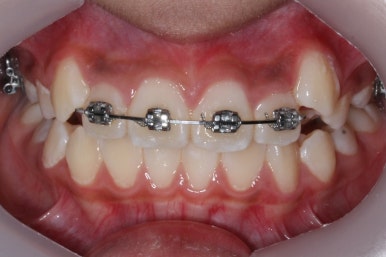

8개월이 지난 모습입니다.

장치는 앞니 4개 + 헤드기어만 사실상 했습니다. 송곳니에는 아무것도 하지 않았죠.

덧니의 변화된 모습이 느껴지시나요?

다시 한 번 말씀드리면 공간확보만 된다면 서서히 좋아지게 됩니다. 100%는 아니기 때문에 추후에 전체적으로 정리를 해줄 필요가 있는데 미리 이렇게 해두면 훨씬 추후에 작업이 간소해지죠.